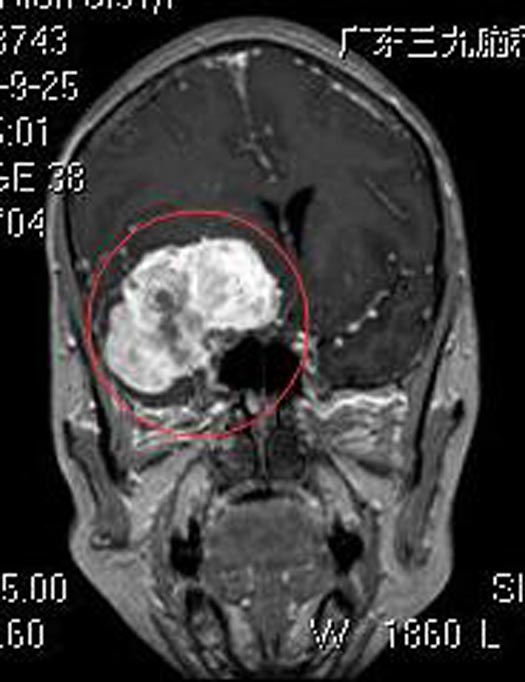

广东三九脑科医院头颅MR检查提示:右侧蝶骨嵴示一跨颅窝生长巨大占位性病变,内示多发流空血管影,大小约为6.4cm×5.2cm×5.4cm。 头颅CTA提示:右侧蝶骨嵴跨前中颅窝巨大占位性病变,血供极其丰富,考虑脑膜瘤。

▲术前MR